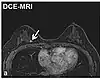

Dynamic contrast enhancedDCEMeasures changes over time in the shortening of the spin–lattice relaxation (T1) induced by a gadolinium contrast bolus.[36] Faster Gd contrast uptake along with other features is suggestive of malignancy (pictured).[37]